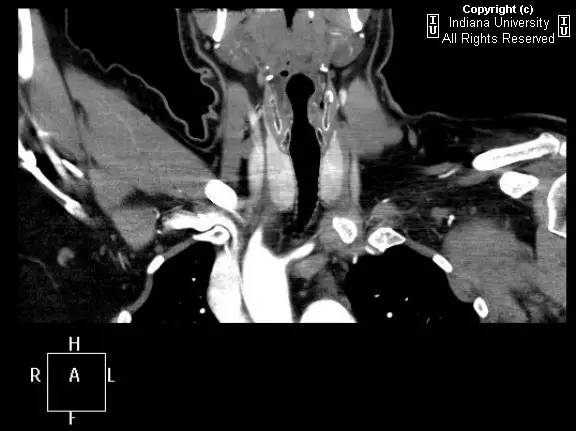

【影像学表现】胸部平片示右位主动脉弓,肺动脉突出,双肺清晰。CT示右位主动脉弓,并右位降主动脉,迷走左锁骨下动脉起自后方,从食管后走形形成血管环。迷走左锁骨下动脉与憩室相关(Kommerell)。食管因左锁骨下动脉及憩室而向前移位。

【诊断】右位主动脉弓并血管环形成、迷走左锁骨下动脉并Kommerell憩室

Right-sided aorticarch, with vascular ring and aberrant left subclavian with Kommerell\’sdiverticulum